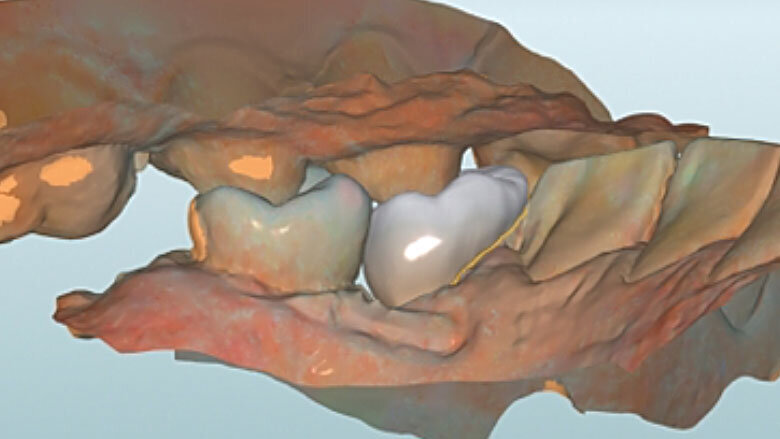

Fig. 5. Tras el escaneo intraoral se estableció el límite de la preparación.

Fig. 6. Mediante un escaneo vestibular se trasladó la intercuspidación habitual.

Antes de la preparación se determinó el color dental 2M2 mediante la VITA Toothguide 3D-MASTER (VITA Zahnfabrik) y se seleccionó la pieza en bruto correspondiente. Se colocó adhesivamente una espiga de fibra de vidrio para incrementar la retención de la posterior reconstrucción de composite. Durante la preparación, únicamente se acortaron las paredes y se incorporó un chamfer en la zona del defecto. Se redondearon sistemáticamente los bordes afilados en la cavidad. Antes del escaneo intraoral fue posible tratar con composite de forma mínimamente invasiva la caries proximal en el diente 34 gracias al buen acceso por mesial.